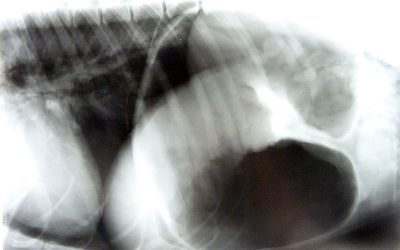

Magendrehung mit Komplikationen Kardioversion

Heute möchte ich…